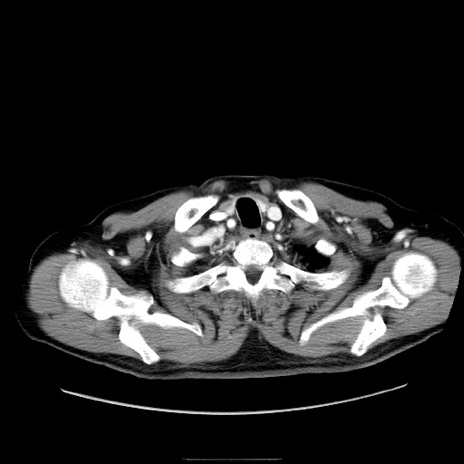

症例30(横断像)

【症例】80歳代男性

【主訴】臍周囲痛

【現病歴】約6時間前から臍下部痛が出現。次第に腹部膨隆・背部痛も生じてきたため来院。背部痛の場所は変化しない。

【身体所見】意識清明、BT 36.3℃、BP  131/87mmHg、P 87bpm、SpO2 100%(RA)、臍周囲自発痛・圧痛あり、反跳痛なし、自発痛部位に一致して板状硬あり、腹部膨隆、腸雑音減弱、CVA tenderness両側陰性。

【データ】WBC 19600、CRP 0.33